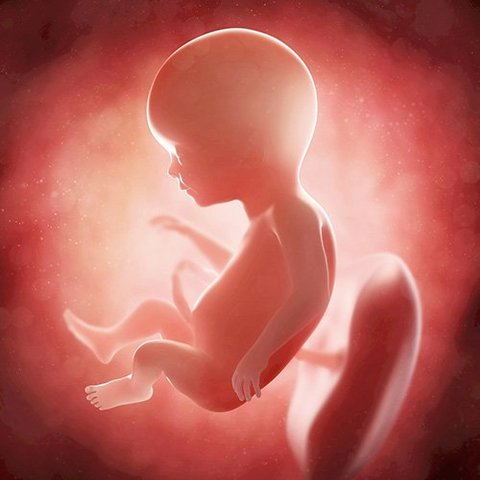

• SEMANA 20

SEMANA 20

el bebé ya cuenta con 18 semanas de vida, a partir de este momento es capaz de oir. sus pulmones y el tubo digestivo están madurando